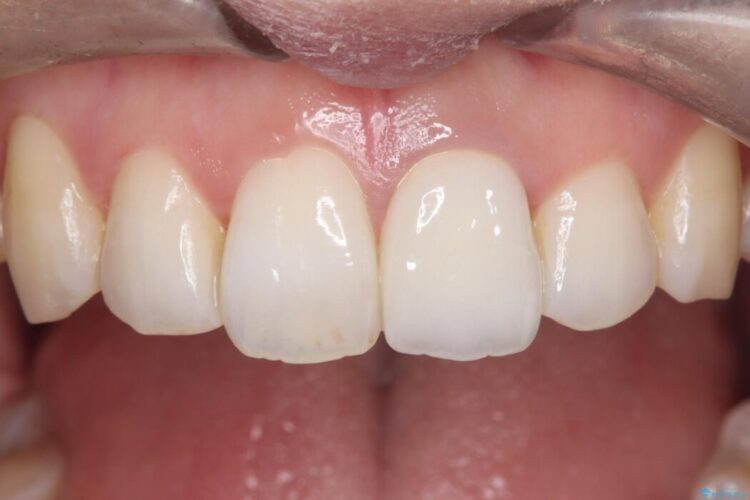

再根管治療とオールセラミックで前歯の気になる変色を解消

再根管治療とオールセラミックで前歯の気になる変色を解消 ビフォー 再根管治療とオールセラミックで前歯の気になる変色を解消 アフター

他院で神経を取った前歯が変色してきたとご相談にいらした患者様です。